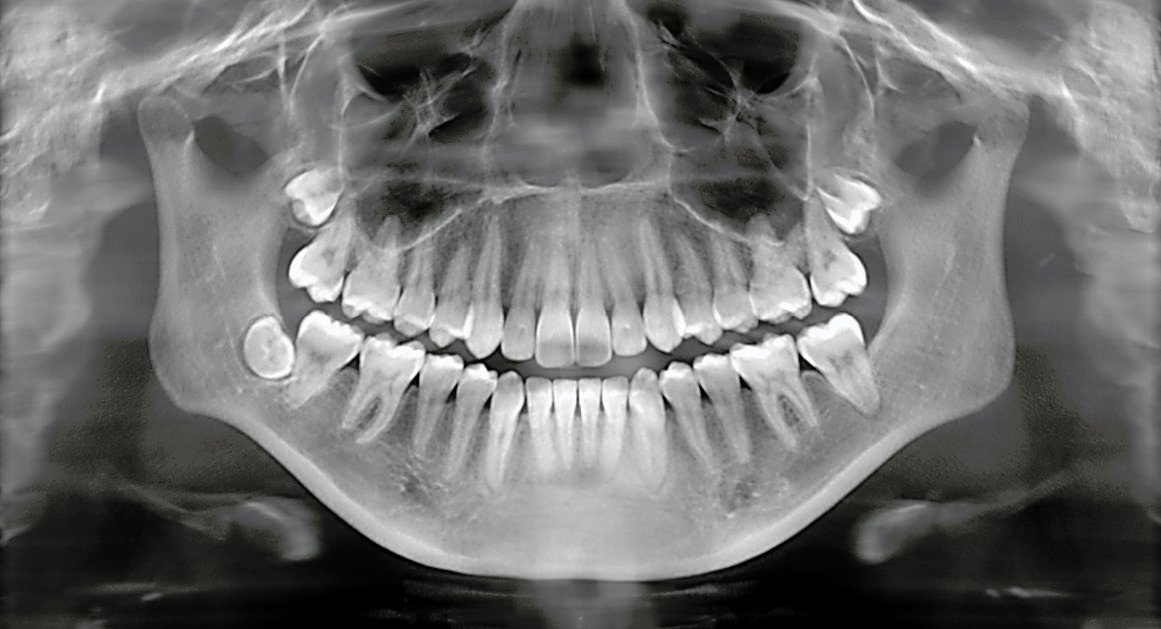

Dr. Saylee uses advanced diagnostic tools like digital X-rays to identify hidden problems such as cavities, gum disease, or early signs of oral infections.

The dentist will examine your teeth, gums, and mouth, take X-rays if necessary, and provide cleaning or treatment guidance.